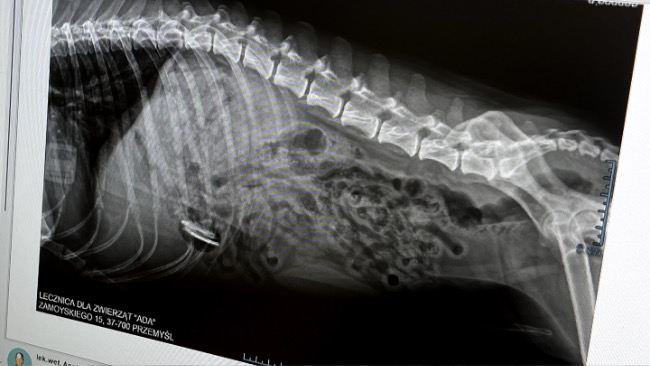

Emergency. Jędruś nagle źle się poczuł. Opiekunowie zareagowali natychmiast i dzięki temu szybko trafił do lekarza. Badanie ujawniło dramatyczną prawdę. W jego brzuchu utknęło ciało obce. Każda godzina zmniejsza jego szanse.